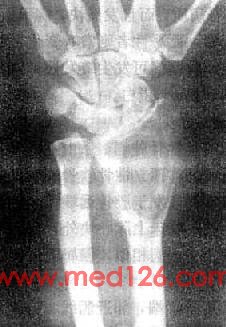

长骨巨细胞瘤的X线表现多较典型(图2-1-23),常侵犯骨端,症变直达骨性关节面下。多数为偏侧性破坏,边界清楚。瘤区X线表现可有两种类型,较多的病例破坏区内可有数量不等、比较纤细的骨嵴。X线上可见似有分隔成为大小不一的小房征,称为分房型。少数病例破坏区内无骨嵴,表现为单一的骨质破坏,称为溶骨型。病变局部骨骼常呈偏侧性膨大,骨皮质变薄,肿瘤明显膨胀时,周围只留一薄层骨性包壳。肿瘤内无钙化或骨化致密影,邻近无反应性骨膜增生。边缘亦无骨硬化带,如不并发骨折也不出现骨膜增生。破坏区骨性包壳不完整,并于周围软组织中出现肿块者表示肿瘤生长活跃。肿瘤边缘出现筛孔状和虫蚀状骨破坏,骨嵴残缺紊乱。侵犯软组织出现明确肿块者,则提示为恶性骨巨细胞瘤。肿瘤一般不穿破关节软骨,但偶可发生,甚至越过关节侵犯邻近骨骼。

图2-1-23 桡骨巨细胞瘤桡骨骨端边界清楚的骨破坏,其中有多个骨隔将骨破坏区分成多个小房,病变有膨胀性